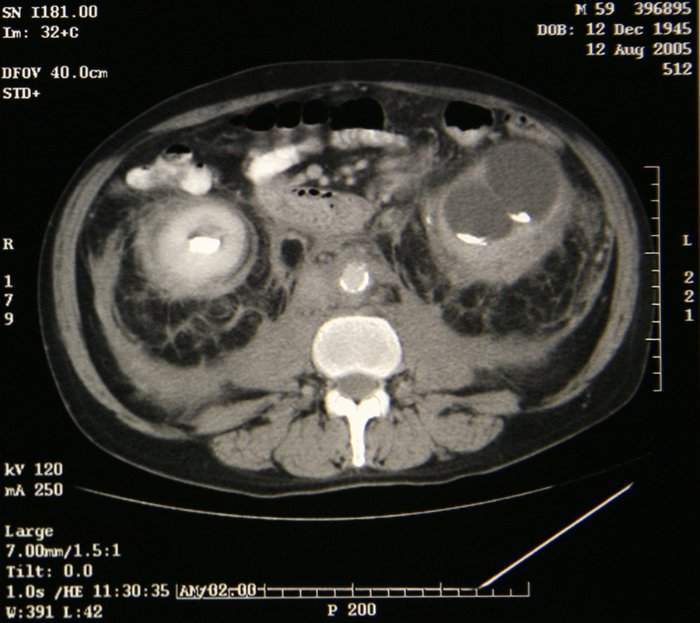

Síndrome de Erdheim-Chester

| actual | 15:39 27 abr 2012 | 700 × 623 (69 KB) | Raida jc.ssp (discusión | contribuciones) | Síndrome de Erdheim-Chester |